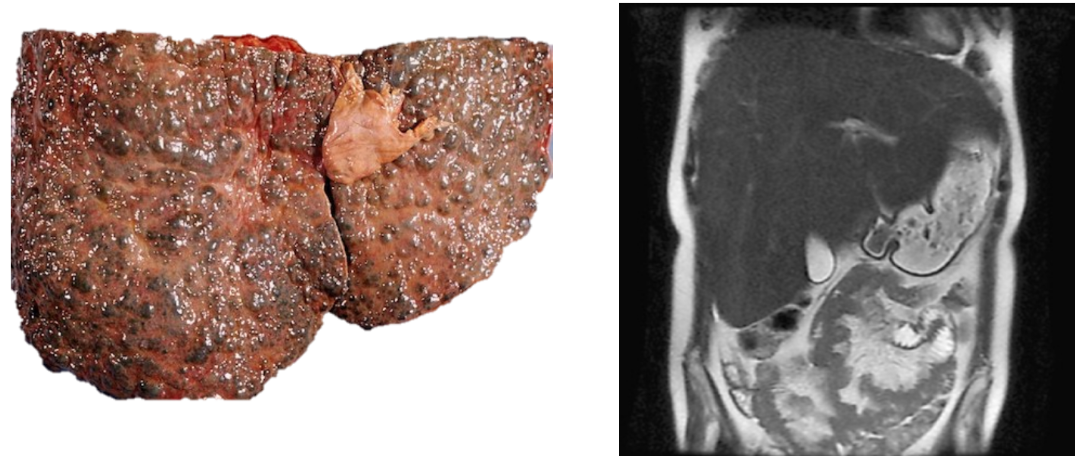

A chronic alcoholic comes into your clinic with dilated veins of the abdominal wall.

Obstruction of blood through liver will cause increased pressure in hepatic portal vein

This can cause enlargement of the spleen and caput medusa